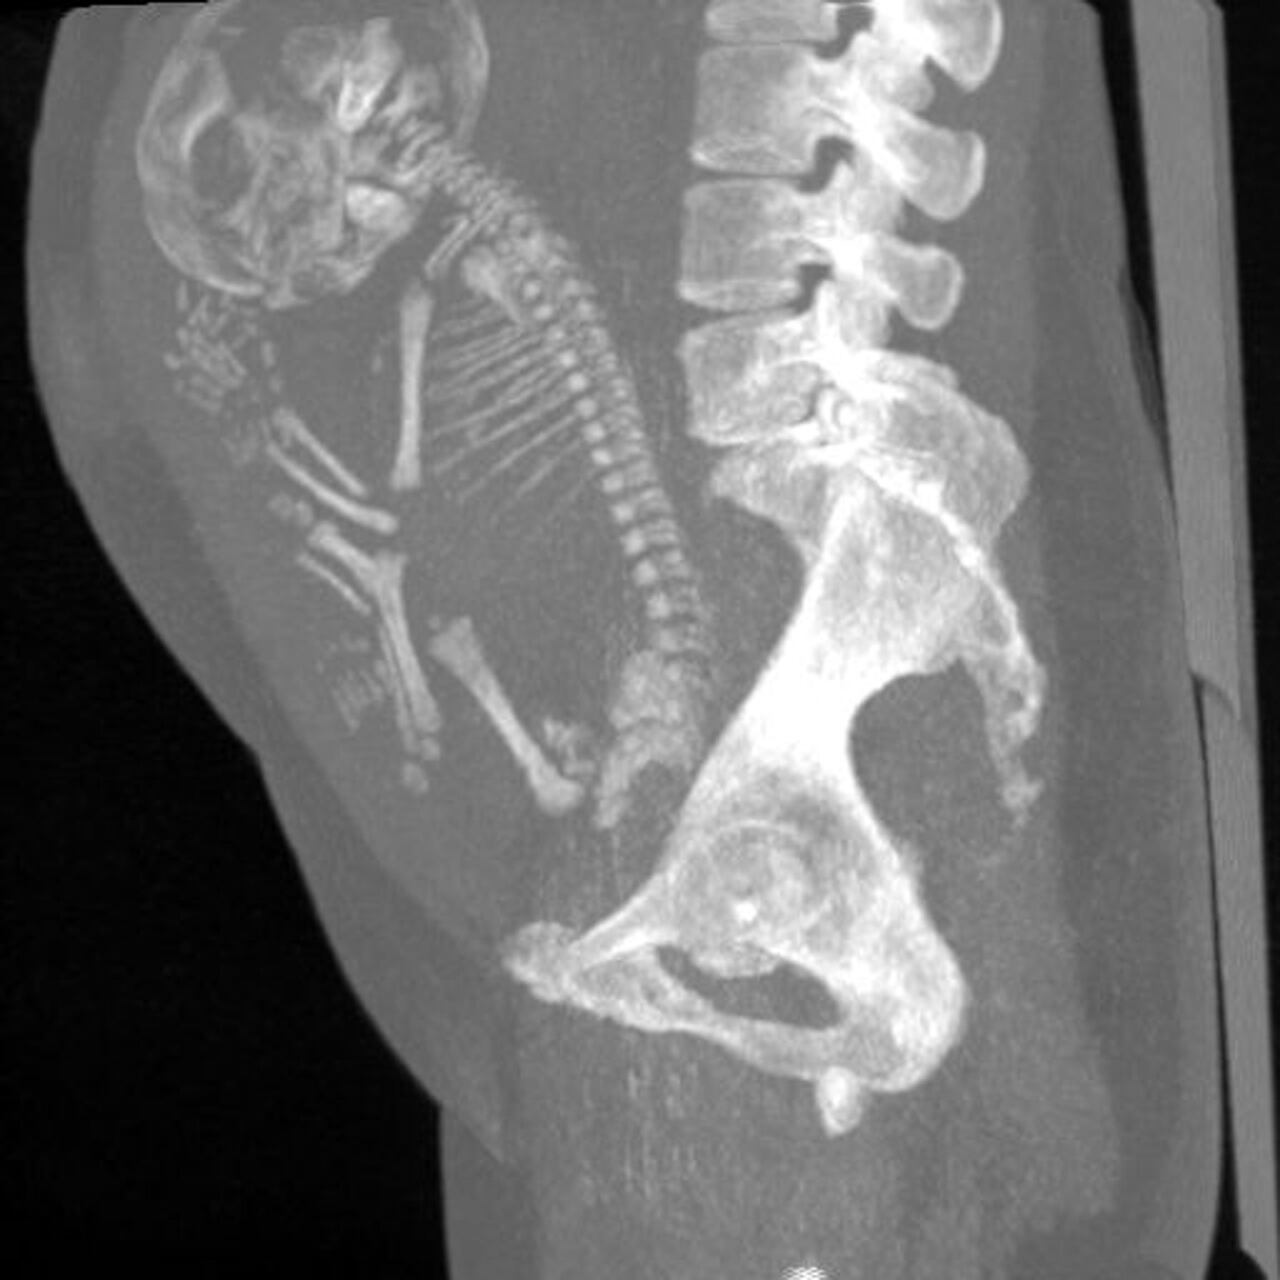

Ciudadanos del Estado de Durango, en México, se encuentran consternados, luego de que se hiciera pública la historia de una mujer de 84 años, a quien le encontraron un feto momificado en su vientre desde hace más de 40 años.

De acuerdo con algunos medios mexicanos, la mujer acudió al médico tras sentir un fuerte dolor abdominal, por lo que le realizaron los estudios de rutina y fue allí donde evidenciaron los restos del bebé, de quien al parecer la mujer nunca tuvo conocimiento de que había estado embarazada.

Así las cosas, se trataría de un embarazo ectópico que se momificó, cuando el feto tenía 40 semanas de gestación, pero nunca le provocó problemas de salud, por lo que pudo seguir con su vida normalmente, hasta ahora, 40 años después.

Este tipo de casos, es denominado en la medicina, como litopedia; proceso que se genera cuando un óvulo fertilizado se adhiere a un lugar fuera del útero. Pese a esto, el feto crece, pero no puede sobrevivir al no contar con el lugar y las condiciones suficientes.

Por esta razón, el cuerpo humano lo identifica como un objeto extraño y se protege envolviéndolo con calcio y lo que se explicaría como el proceso de momificación. Cabe señalar que en el mundo solo se han registrado 300 casos de litopedia.